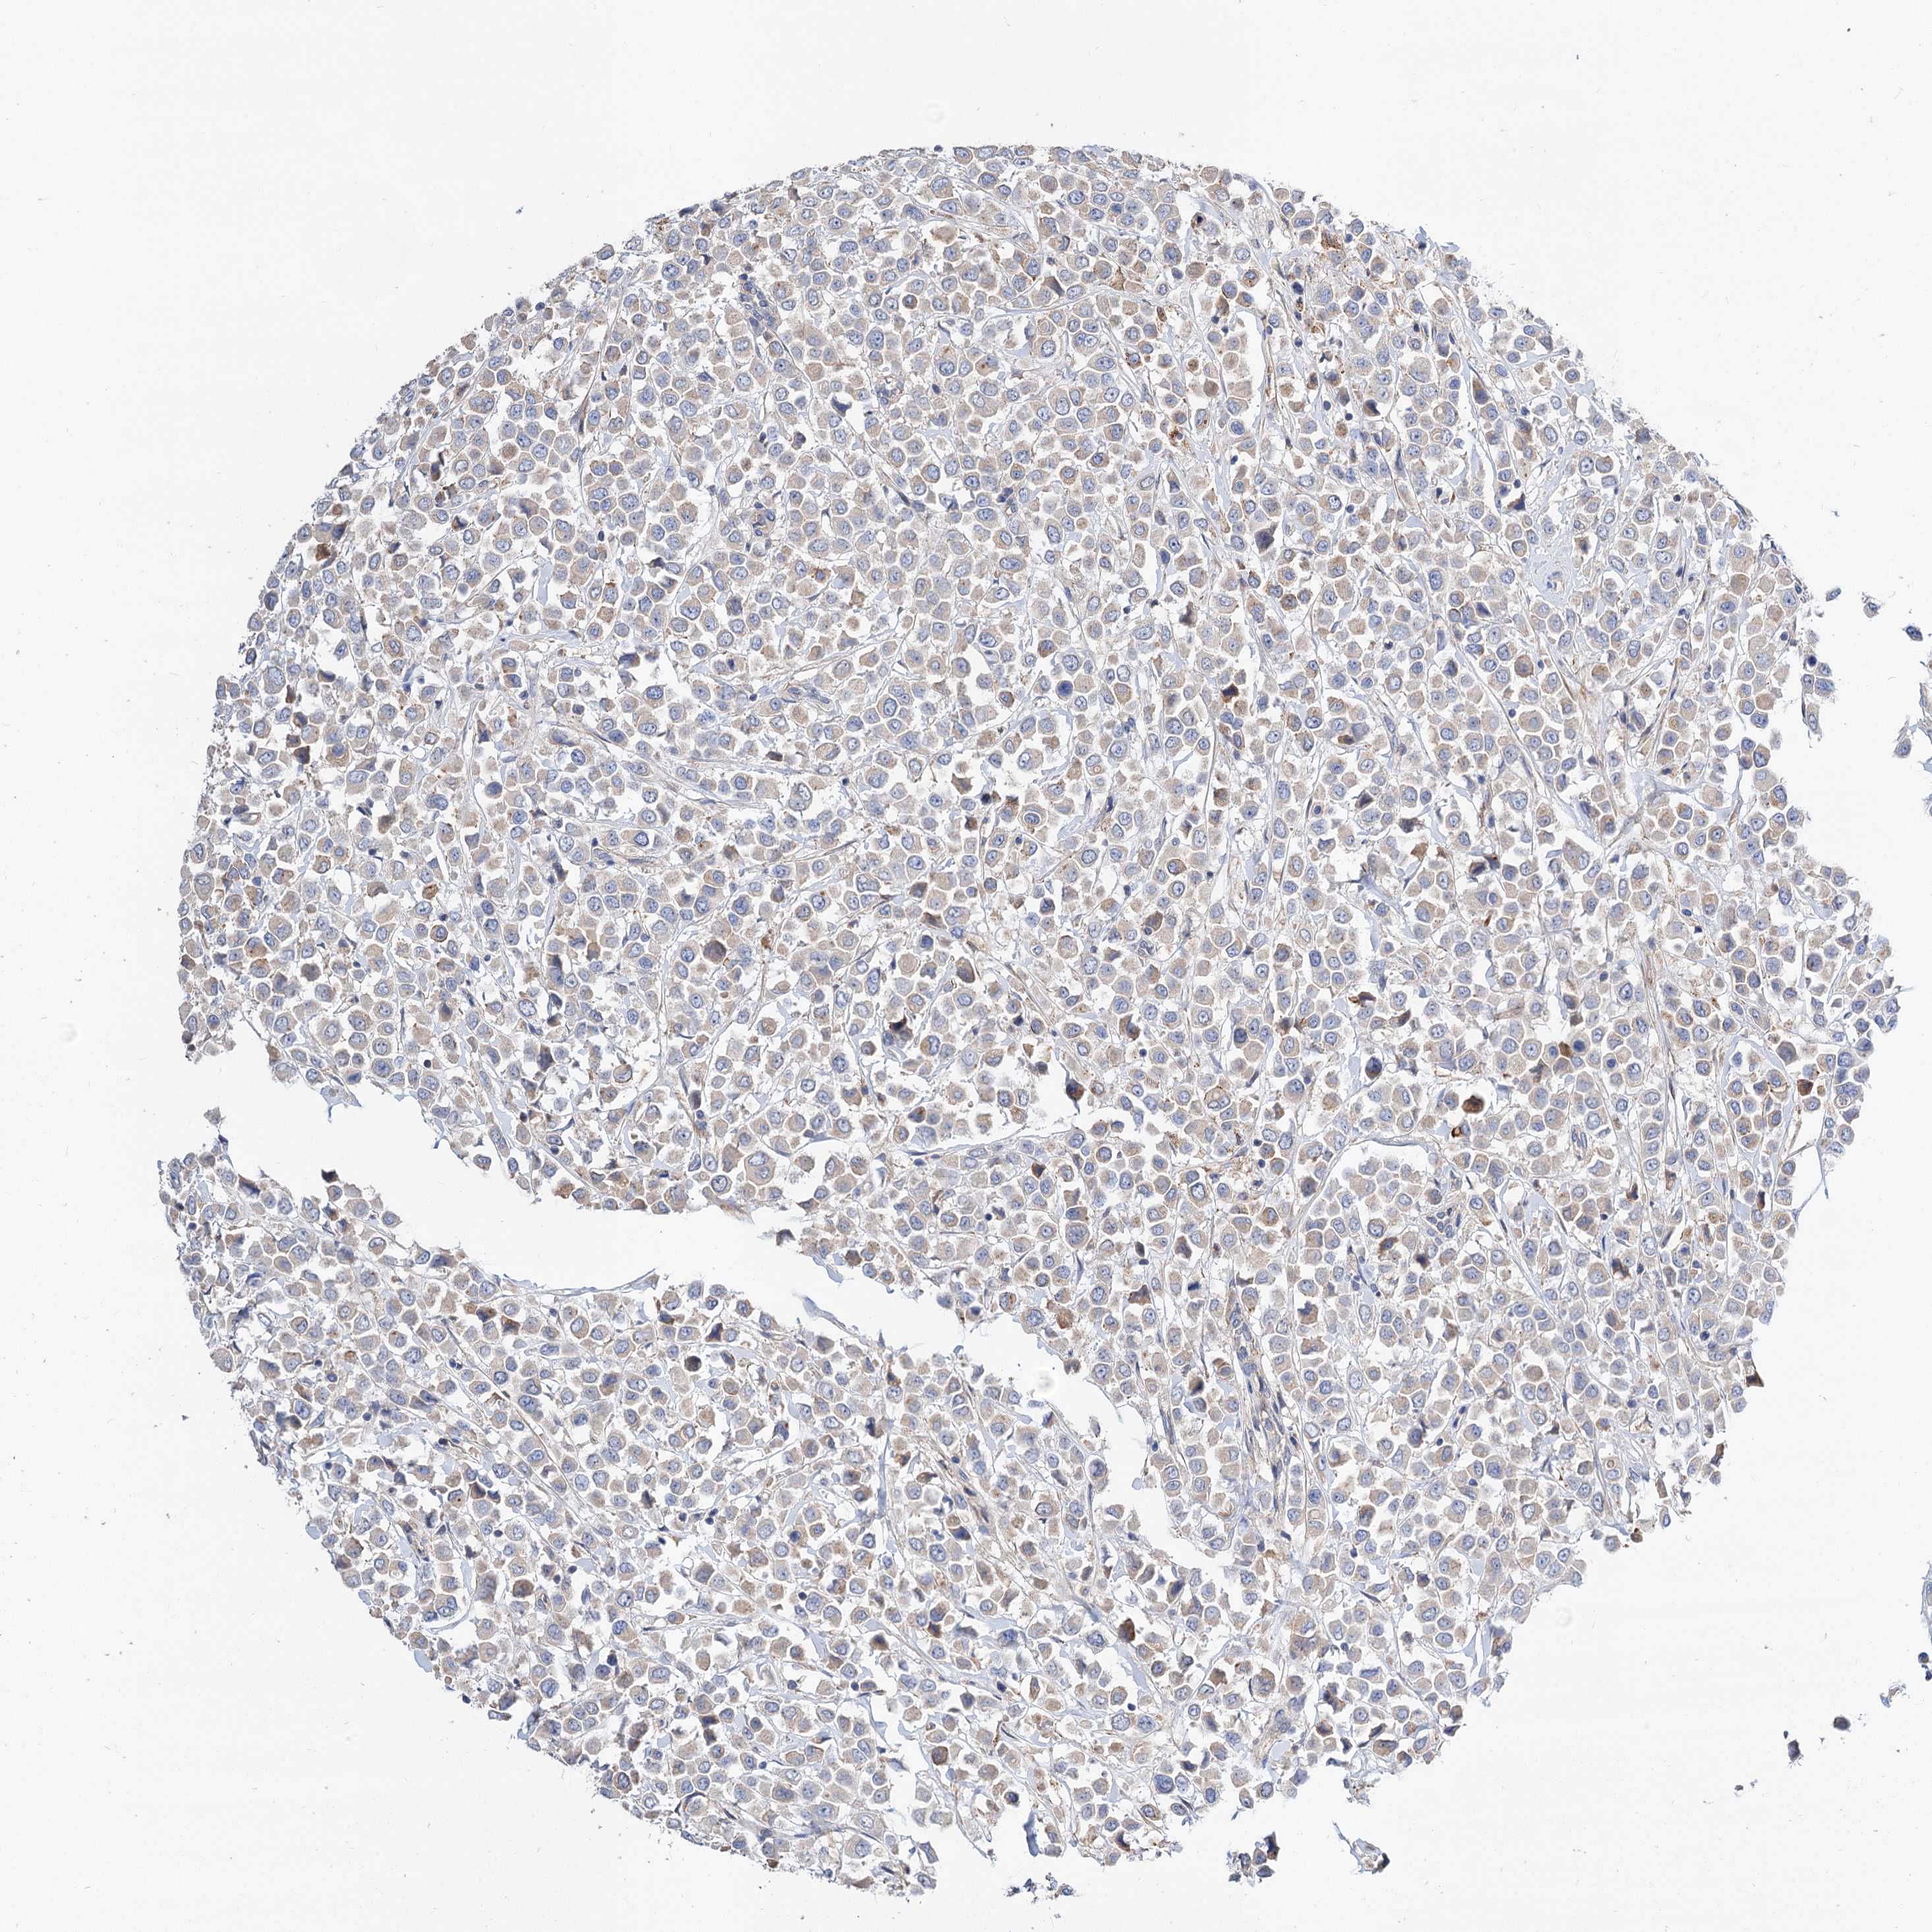

CANCER BREAST CANCER Show tissue menu

BRCA TCGA BRCA VALIDATION PROTEIN EXPRESSION